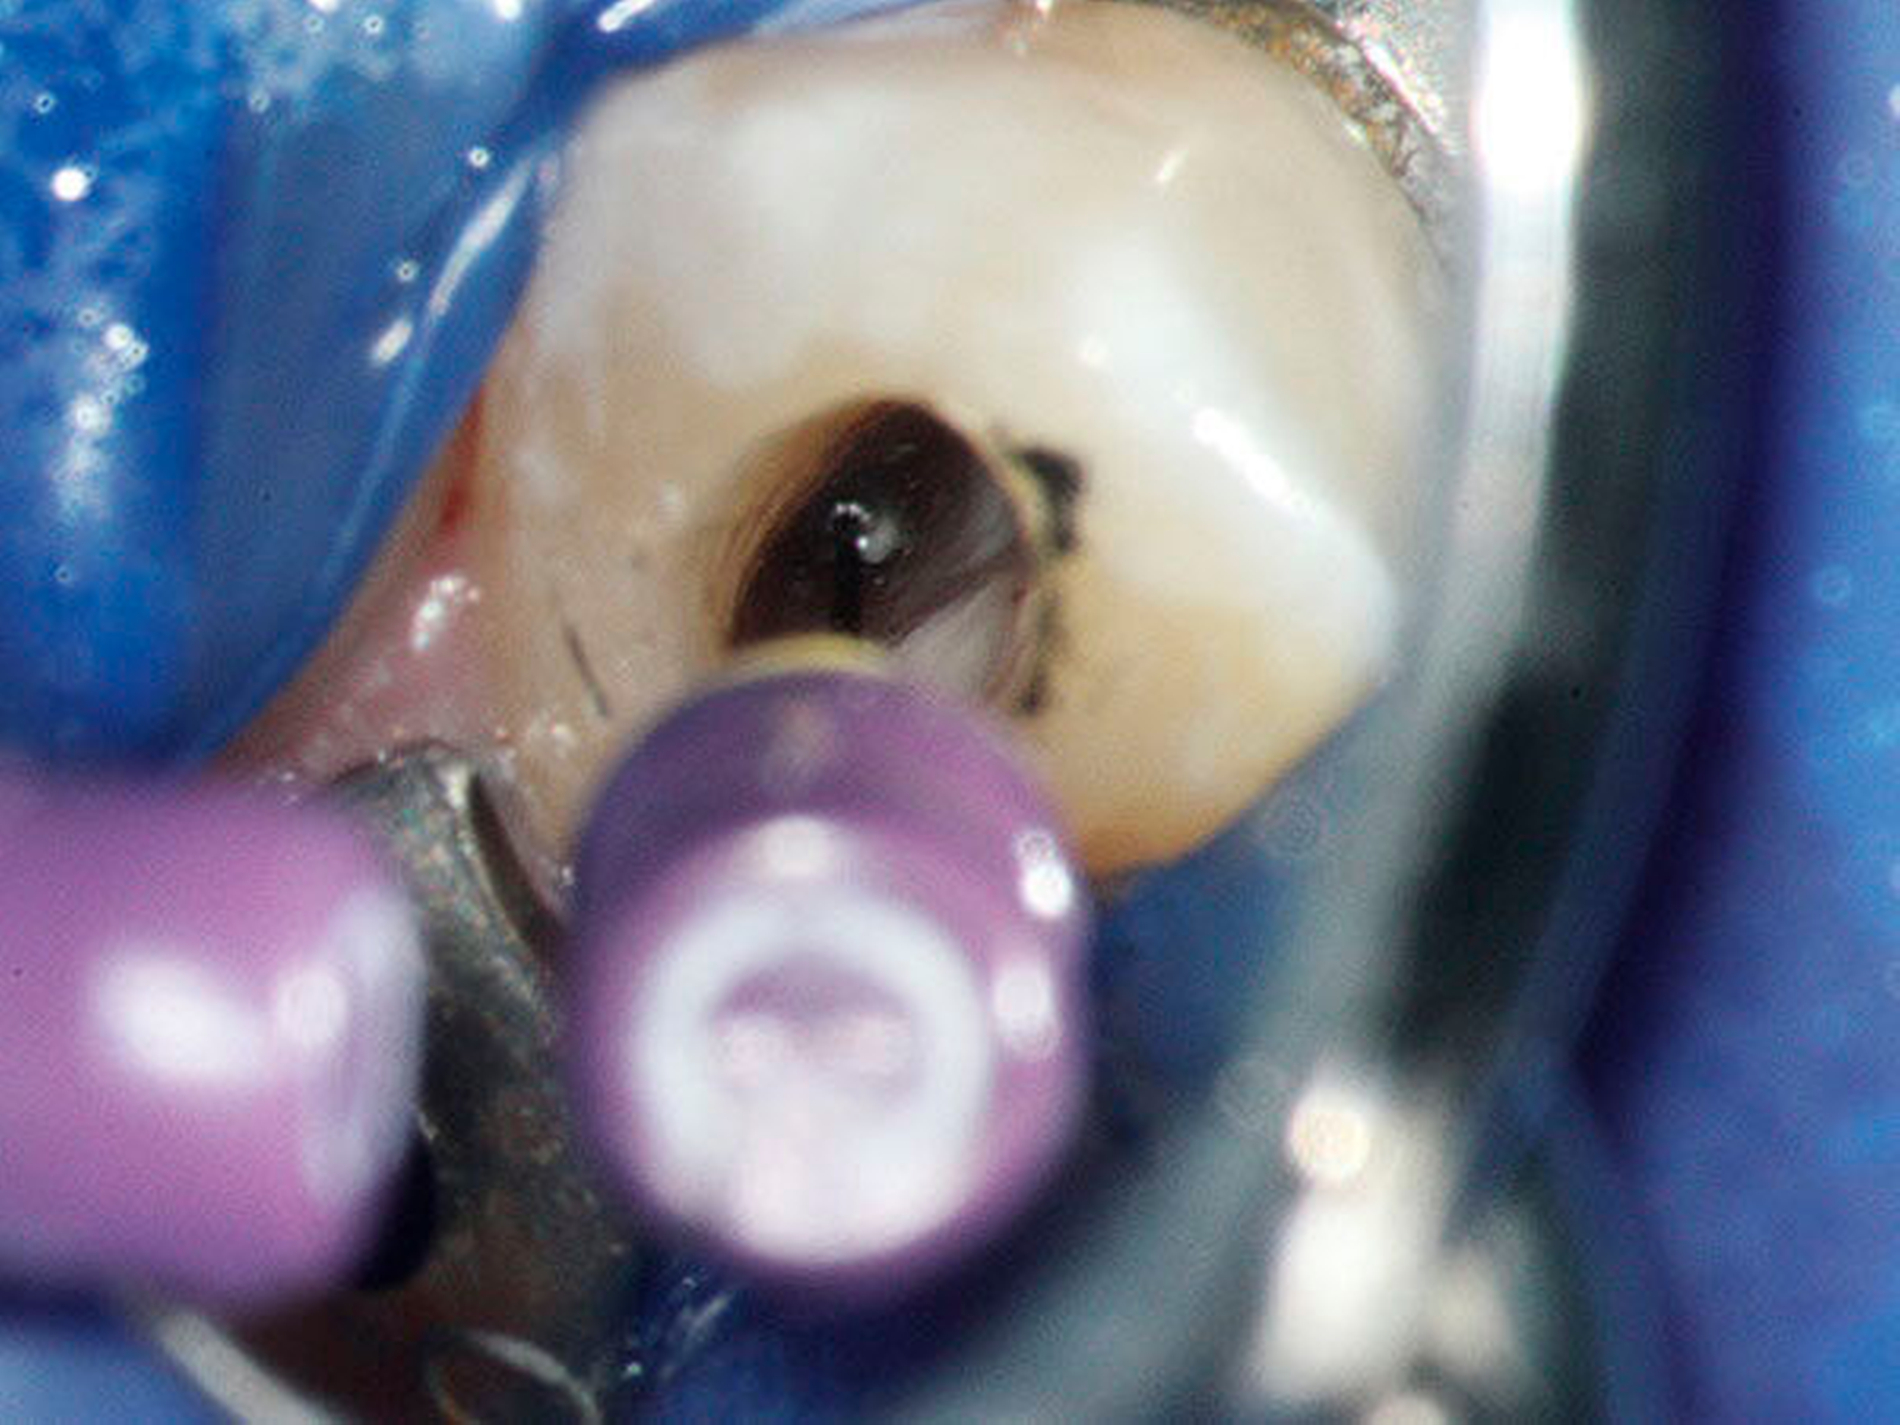

Es erfolgte die Inspektion unter dem OP-Mikroskop. Klinisch zeigte sich kein Anhalt auf Kanalstrukturen. Es erfolgten zwei zeitintensive Sitzungen, in denen der Wurzelkanal nicht dargestellt werden konnte und der Zahn, trotz größter Vorsicht und Verwendung des Mikroskops, perforiert wurde. Die Perforation war vestibulär im mittleren Kanaldrittel nach einer Länge von 18 mm lokalisiert (Abbildungen 3 und 4). Die Therapieentscheidung fiel daraufhin zugunsten einer „Guided Endodontics“-Behandlung.

In der folgenden Sitzung wurde die Schiene angepasst (Abbildung 10), die Trepanationsöffnung ergänzt und die Bohrung mittels Endoseal-Bohrer auf die zuvor am DVT geplante Tiefe vorgenommen. Nach erfolgter Bohrung wurde der Kofferdam angebracht und das erschlossene Kanalsystem mit einer ISO 10 C-Feile sondiert (Abbildung 11). Die Endometrie ergab 23,5 mm. Eine Röntgenkontrastaufnahme mit einer ISO 15 K-Feile wurde angefertigt (Abbildung 12). Die mechanische Wurzelkanalpräparation erfolgte mit Reciproc Blue 25 und 40 (VDW, München), die Desinfektion mit NaOCl 5 Prozent und EDTA 17 Prozent. Die Perforation wurde mit Total Fill BC Root Repair Material (FKG, La Chaux-de-Fonds, Schweiz) abgedeckt (Abbildung 13). Im Anschluss wurde eine Masterpointaufnahme angefertigt (Abbildung 14), der Wurzelkanal mit Total Fill BC Points und Sealer (FKG, La Chaux-de-Fonds, Schweiz) biokeramisch abgefüllt (Abbildung 15) und adhäsiv verschlossen. Bei der klinischen Nachuntersuchung nach vier Wochen war der Zahn symptomlos.